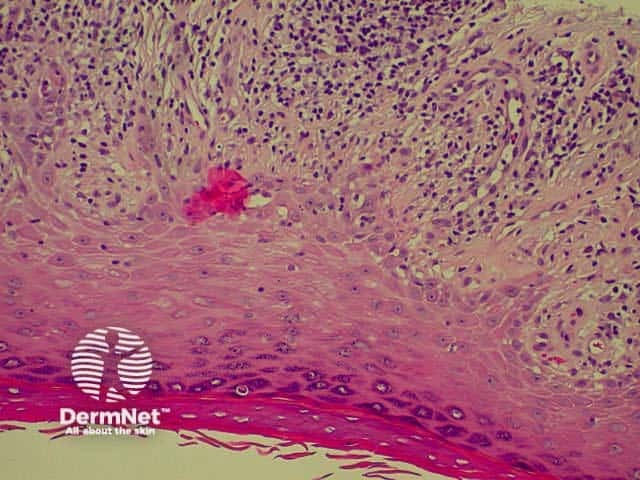

Bullous pemphigoid is the most common subepidermal blistering disease. Link to a clinical description of bullous pemphigoid.

The histological features of bullous pemphigoid are:

Direct immunofluorescence reveals IgG and complement deposits in the basement membrane zone. (Biopsies for fluorescence should ideally be taken from erythematous but not yet bullous areas.) Indirect immunofluorescence will detect circulating antibodies. ELISA will be positive to 180 and 230kd BP antigens 2 and 1 respectively. Using skin separated by a salt splitting process, immunoreactants are seen to bind to the roof of the blister.

Bullous pemphigoid Bullous pemphigoid Bullous pemphigoid